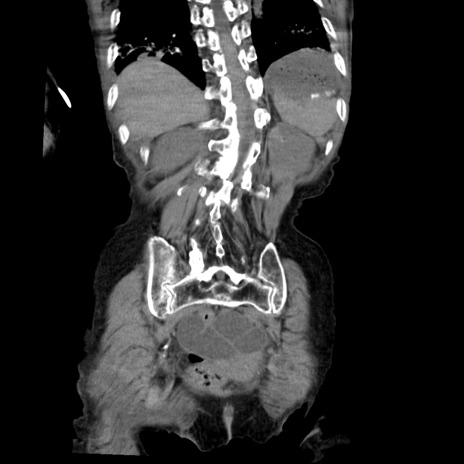

症例27(冠状断像)

【症例】80歳代女性

【主訴】嘔吐、腹痛

【現病歴】数時間前より嘔吐あり。心窩部痛出現し、徐々に右下腹痛あり。その後も数回嘔吐あり救急搬送となる。

【既往歴】左大腿骨頚部骨折手術

【身体所見】腹部は膨隆しているが軟らかく圧痛なし。腸雑音はやや亢進。

【データ】WBC 12000、CRP 19.05